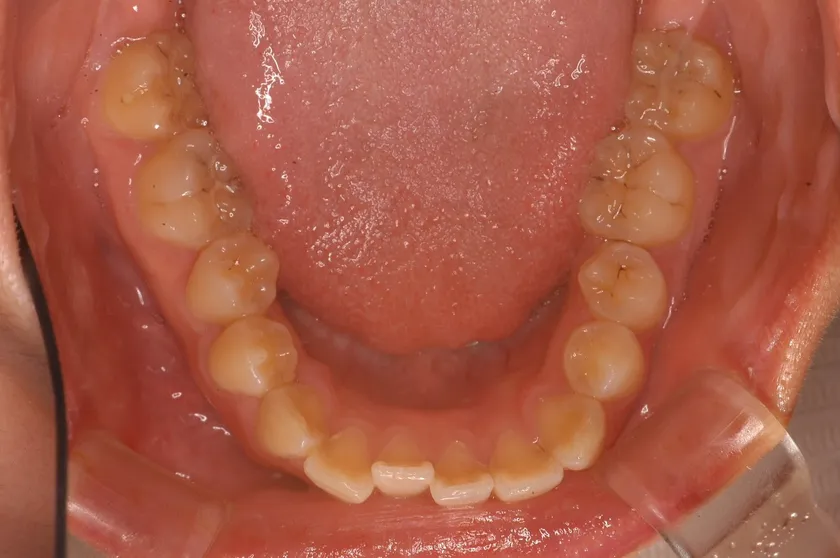

現代人に多い歯並び

「理想的な歯並び」と「現代人に多い歯並び」の画像、これは何を意味しているのか?

歯並びの中にあるもの。それは、「舌」だったのです。

歯並びが小さいと「舌が窮屈」になり、アゴの位置がずれてしまいます。